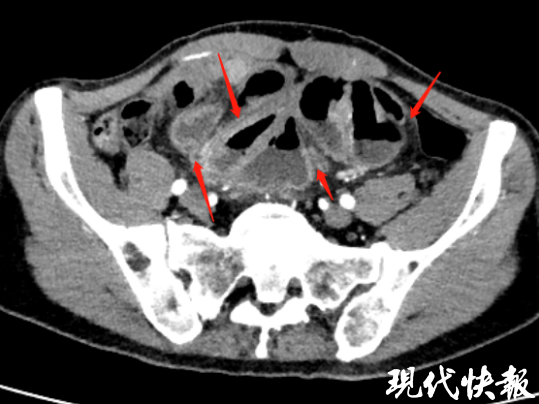

科主任顧新華接診后,結(jié)合劉先生的病史和癥狀,安排了針對(duì)性檢查。術(shù)前CT顯示劉先生的小腸有被纖維膜包裹的“繭狀”結(jié)構(gòu)、腹膜增厚、鈣化等特征,經(jīng)過綜合系統(tǒng)評(píng)估,一個(gè)罕見的診斷結(jié)果浮出水面——腹繭癥。

現(xiàn)代快報(bào)記者了解到,腹繭癥是一種臨床發(fā)病率極低的腹腔疾病,患者的小腸會(huì)被一層致密、堅(jiān)韌的纖維膜緊緊包裹,形似“蠶繭”,進(jìn)而導(dǎo)致腸管粘連、腸梗阻,嚴(yán)重影響消化功能。該疾病發(fā)病率極低,手術(shù)治療難度極大,對(duì)醫(yī)生的技術(shù)水平和臨床經(jīng)驗(yàn)都是巨大考驗(yàn)。